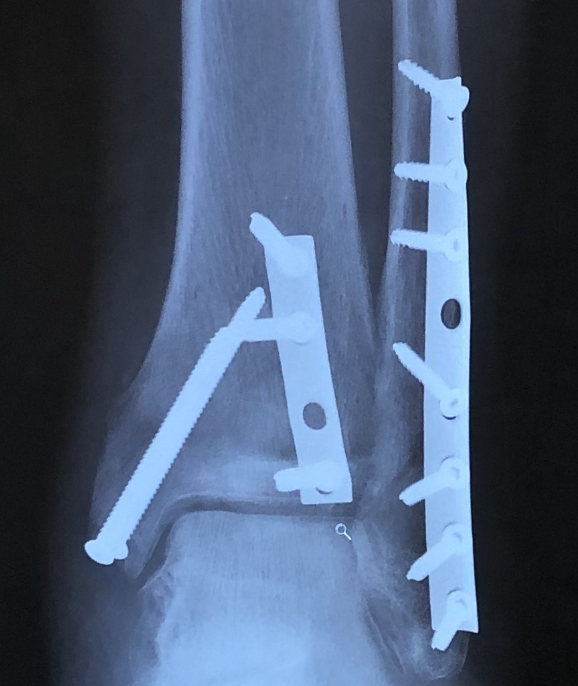

After sustaining a trimalleolar fracture of my left ankle on July 15,2020, Dr. David S. Levine came highly recommended. After my first appointment, he exceeded all trustworthy expectations. Dr. Levine and his (PA) Lauren Buchwald took the time to answer all my questions.